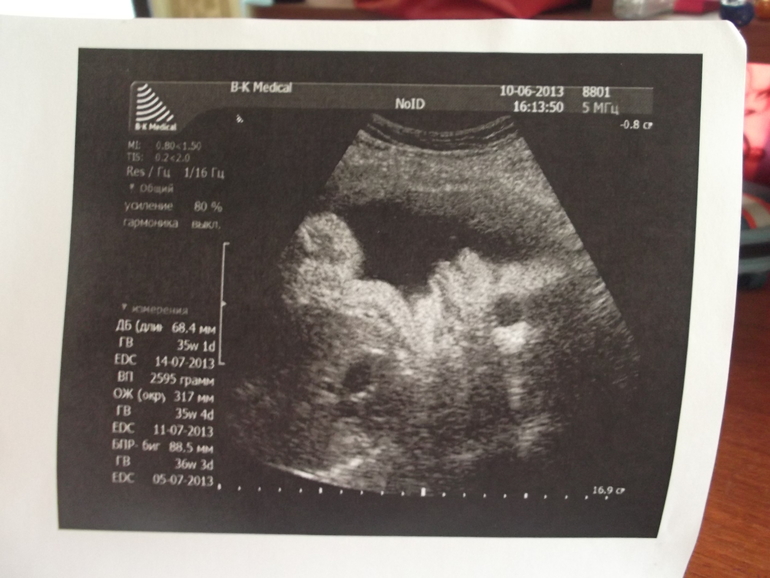

1. Мне приспичило на сроке 35 недель сходить на платное узи с любимым, чтобы ему показали сыночку и сделать его памятную фоточку, но так как малыш уже большой, было это сделать трудно, сыночка сморщился так, что на фото похож на уточку